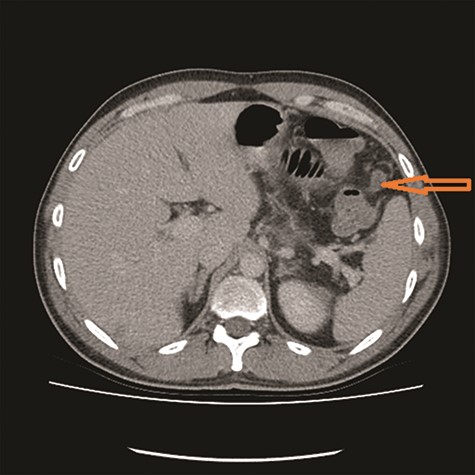

CT showed high-grade proximal jejunal obstruction secondary to a locally infiltrative jejunal mass (Fig. 1) suspicious for carcinoma. There was disseminated peritoneal carcinomatosis with a small volume of ascites and two hepatic metastases (Figs 2–4). A liver biopsy confirmed metastatic deposit of intestinal origin that was positive for CK20 and CDX2 and negative for CK7 and TTF1. There was a mutation in codon 61 of the NRAS gene with no sign of microsatellite instability. Diagnosis of jejunal adenocarcinoma was made.